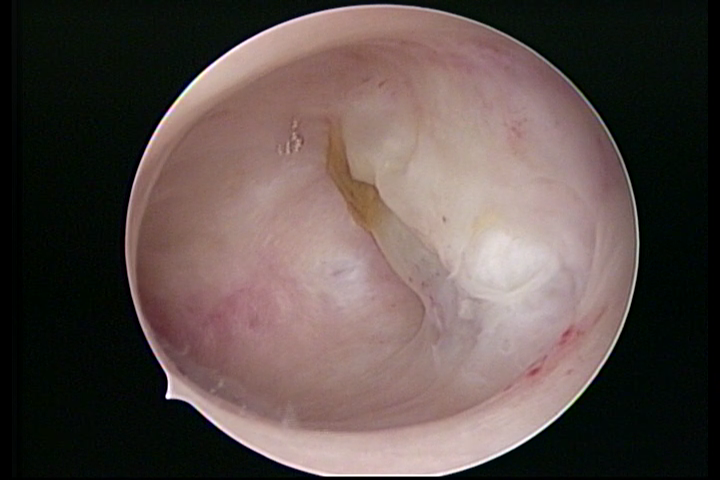

• SINÉQUIA TIPO FIBROSA